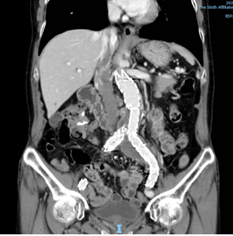

术前CT等影像资料:动脉瘤

术前CTA重建提示:腹主动脉远段、双侧髂总动脉、左侧髂内动脉管腔扩张,左侧髂总动脉瘤最大直径超过42mm。